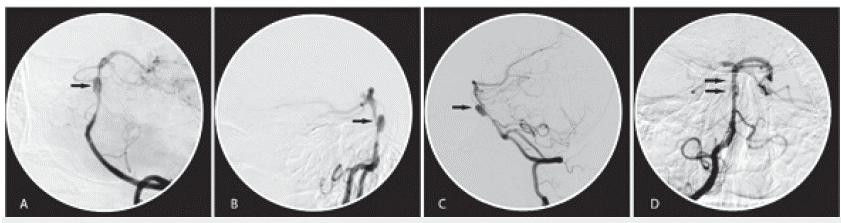

La resonancia magnética nuclear de cerebro con angiografía (RMN) evidencia lesión isquémica aguda en tercio medio lateral izquierdo de la protuberancia (figura 1A y 1B). Secuencias de angiorresonancia: área de estenosis e irregularidad de la pared de la arteria basilar (figura 1C y 1D). La panangiografía cerebral corrobora aneurisma disecante del tercio medio de la arteria basilar de 8,5 mm y cuello ancho (5,8 mm) con zona de estenosis supralesional (figura 2A, 2B, 2C).

Panangiografía cerebral. A. Oblicua. B. Lateral derecha. C. Lateral izquierda. Se aprecia aneurisma disecante del tercio medio de la arteria basilar con zona de estenosis supralesional por disección (flechas negras). D. Vista AP inmediatamente posterior a implante de dispositivo, recanalización del vaso y aislamiento de lesión aneurismática (flechas negras).

Figura 2: Panangiografía cerebral. A. Oblicua. B. Lateral derecha. C. Lateral izquierda. Se aprecia aneurisma disecante del tercio medio de la arteria basilar con zona de estenosis supralesional por disección (flechas negras). D. Vista AP inmediatamente posterior a implante de dispositivo, recanalización del vaso y aislamiento de lesión aneurismática (flechas negras).

Con el diagnóstico de aneurisma disecante de la arteria basilar y una vez controladas las cifras tensionales, decidimos en conjunto con medicina interna y radiología intervencionista el abordaje de la lesión mediante colocación de dispositivo FRED (Flow-Redirection Endoluminal Device) de 3,5 x 22 mm, en intento de aislar el aneurisma. Se ubicó catéter guía en segmento V2 derecho y se procedió a avanzar microcatéter y microguía. Se logró rebasar distalmente la estenosis, se avanzó y se desplegó satisfactoriamente el dispositivo, de modo que cubrió el segmento estenótico y el cuello del aneurisma. Se verificó permeabilidad de todos los vasos post stent y se observó la exclusión del aneurisma y la permeabilización del vaso afectado (figura 2D), que se ha mantenido como corrobora panangiografía evolutiva luego de un año (figura 3). La paciente inicialmente recibe doble antigaregación con ácido acetil salicílico (ASA) 100 mg/día y clopidogrel 75 mg/día durante seis meses. En la actualidad, ASA 100 mg/día, en seguimiento habitual en la consulta, asintomática en todos los controles.